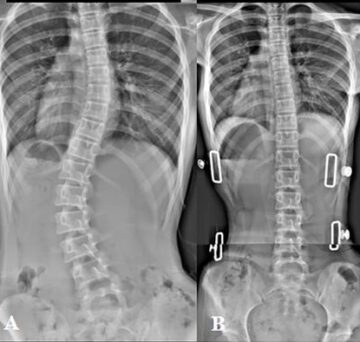

تأثير اختيار أماكن الضغط داخل حزام اعوجاج العمود الفقري على تصحيح الانحناء يُعد حزام اعوجاج العمود الفقري من أهم الأدوات العلاجية غير الجراحية التي تُستخدم لتصحيح الانحناءات في العمود الفقري عند الأطفال والمراهقين. ومع